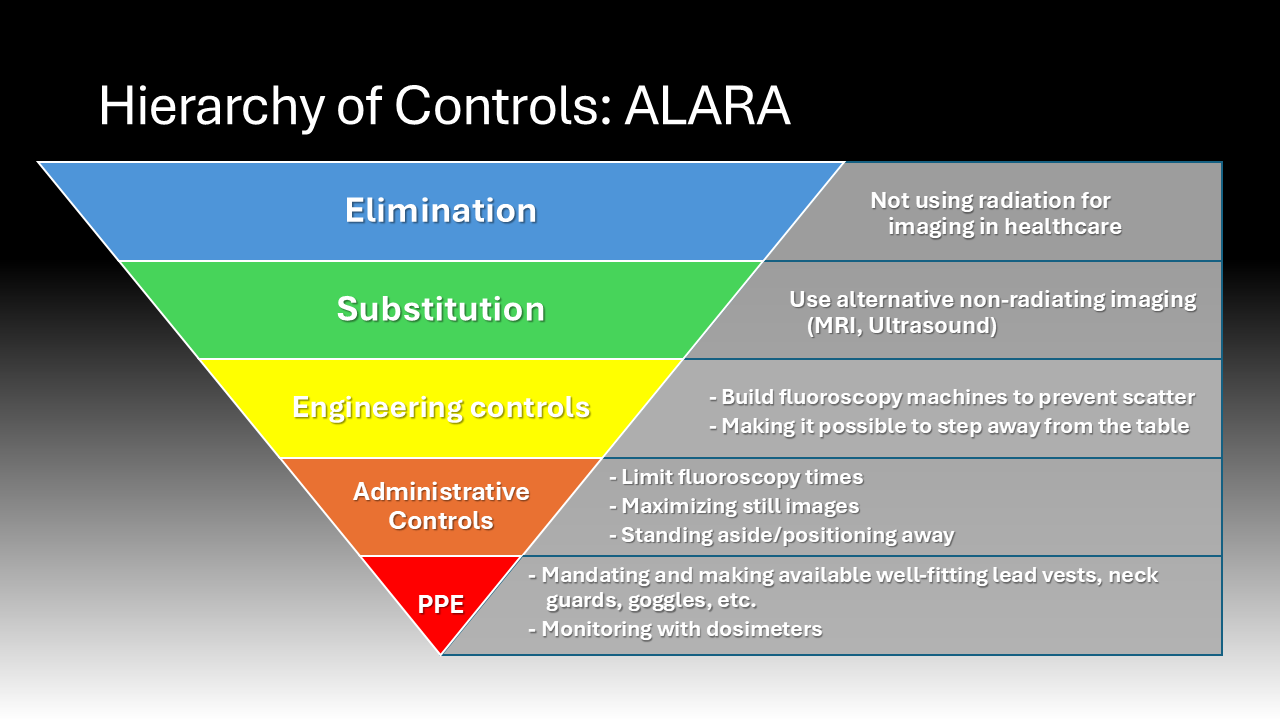

In the operating room, the core tenet of risk mitigation from intraoperative radiation exposure is known as “ALARA,” as low as reasonably achievable.6 This means surgeons are encouraged to use the lowest amount of radiation to achieve a safe surgical environment and outcome.6 To achieve ALARA, it is essential that surgeons wear dosimeters while in the OR to quantify their radiation exposure so it can be tracked by hospital occupational safety experts.15 Understanding their exposure is essential to alert them to their increased risk so they can accordingly mitigate radiation exposure. Many organizations and institutions set dose limits for radiation exposure for their physicians. For instance, the Cleaveland Clinic, a leader in the medical field sets the following annual limits of radiation exposure for their physicians: a maximal total effective/body dose (0.5 Sv), deep or organ dose (0.5 Sv), shallow/whole body skin dose (0.5 Sv), eye exposure (0.15 Sv), and special recommendations for pregnant women (0.005 Sv during pregnancy) and employees under 18 years of age (0.005 Sv).6

Several practices in the operative setting can reduce the quantity and severity of radiation exposure.6 These range from the most effective practices on the hierarchy of controls including elimination and substitution of ionizing rays for other imaging techniques to donning personal protective equipment. Ideally, new advancements in imaging technology would allow the substitution of ionizing radiation for safer imaging modalities which may include magnetic resonance imaging (MRI) or ultrasound. Additionally, there is also a lot of effort being allocated towards developing new intraoperative imaging modalities that use lower doses of X-ray without sacrificing the image quality and utility.6 Unfortunately, while ionizing radiation use intraoperatively could be substituted in future, it is currently still a mainstay in the operating room. Surgeons are encouraged to mitigate their risk of radiation exposure through the ways they use intraoperative imaging. For instance, using single images, slow frame and pulse rates, low magnification, and short fluoroscopy run times when feasible can reduce their exposure.6

Behavioral modifications and personal protective equipment also play a key role in risk mitigation for those exposed to intraoperative radiation.4 When surgeons stand further away from the radiation source, they are exposed to an inversely proportionally decreased dose of radiation.4 Additionally, simply standing on the same side as the receiver significantly reduces the exposure to the scattering radiation as it bounces off the receiver.4 Following the establishment of the Advisory Committees on X-Ray and Radium Protection in the late 1920s, recommendations and regulations requiring the availability and use of lead protection devices and shielding devices have significantly curbed the negative effects of intraoperative scatter radiation exposure.16 These policies were adopted by the Occupational Health and Safety Administration (OSHA) and local hospitals, such as Stony Brook University Hospital.17–20 Lead aprons can reduce exposure by up to 90%, lead collars can reduce thyroid exposure 9-fold, lead gloves can reduce hand exposure by 75%, lead glasses can reduce exposure by up to 70%, and shields can offer significant reductions.4,21